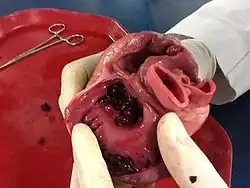

Острый инфаркт миокарда является одной из клинических форм ишемической болезни сердца, протекающей с развитием ишемического некроза участка миокарда, обусловленного абсолютной или относительной недостаточностью его кровоснабжения.

Эндокардит